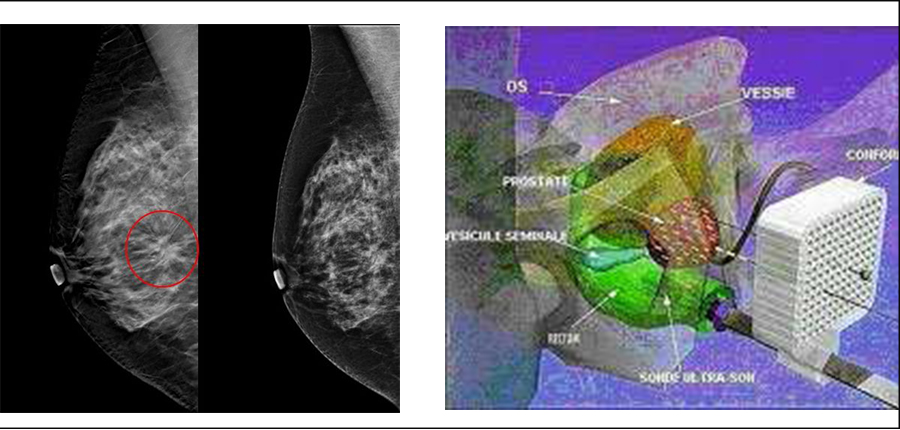

La Thermo ablation du nodule thyroïdien comme alternative thérapeutique